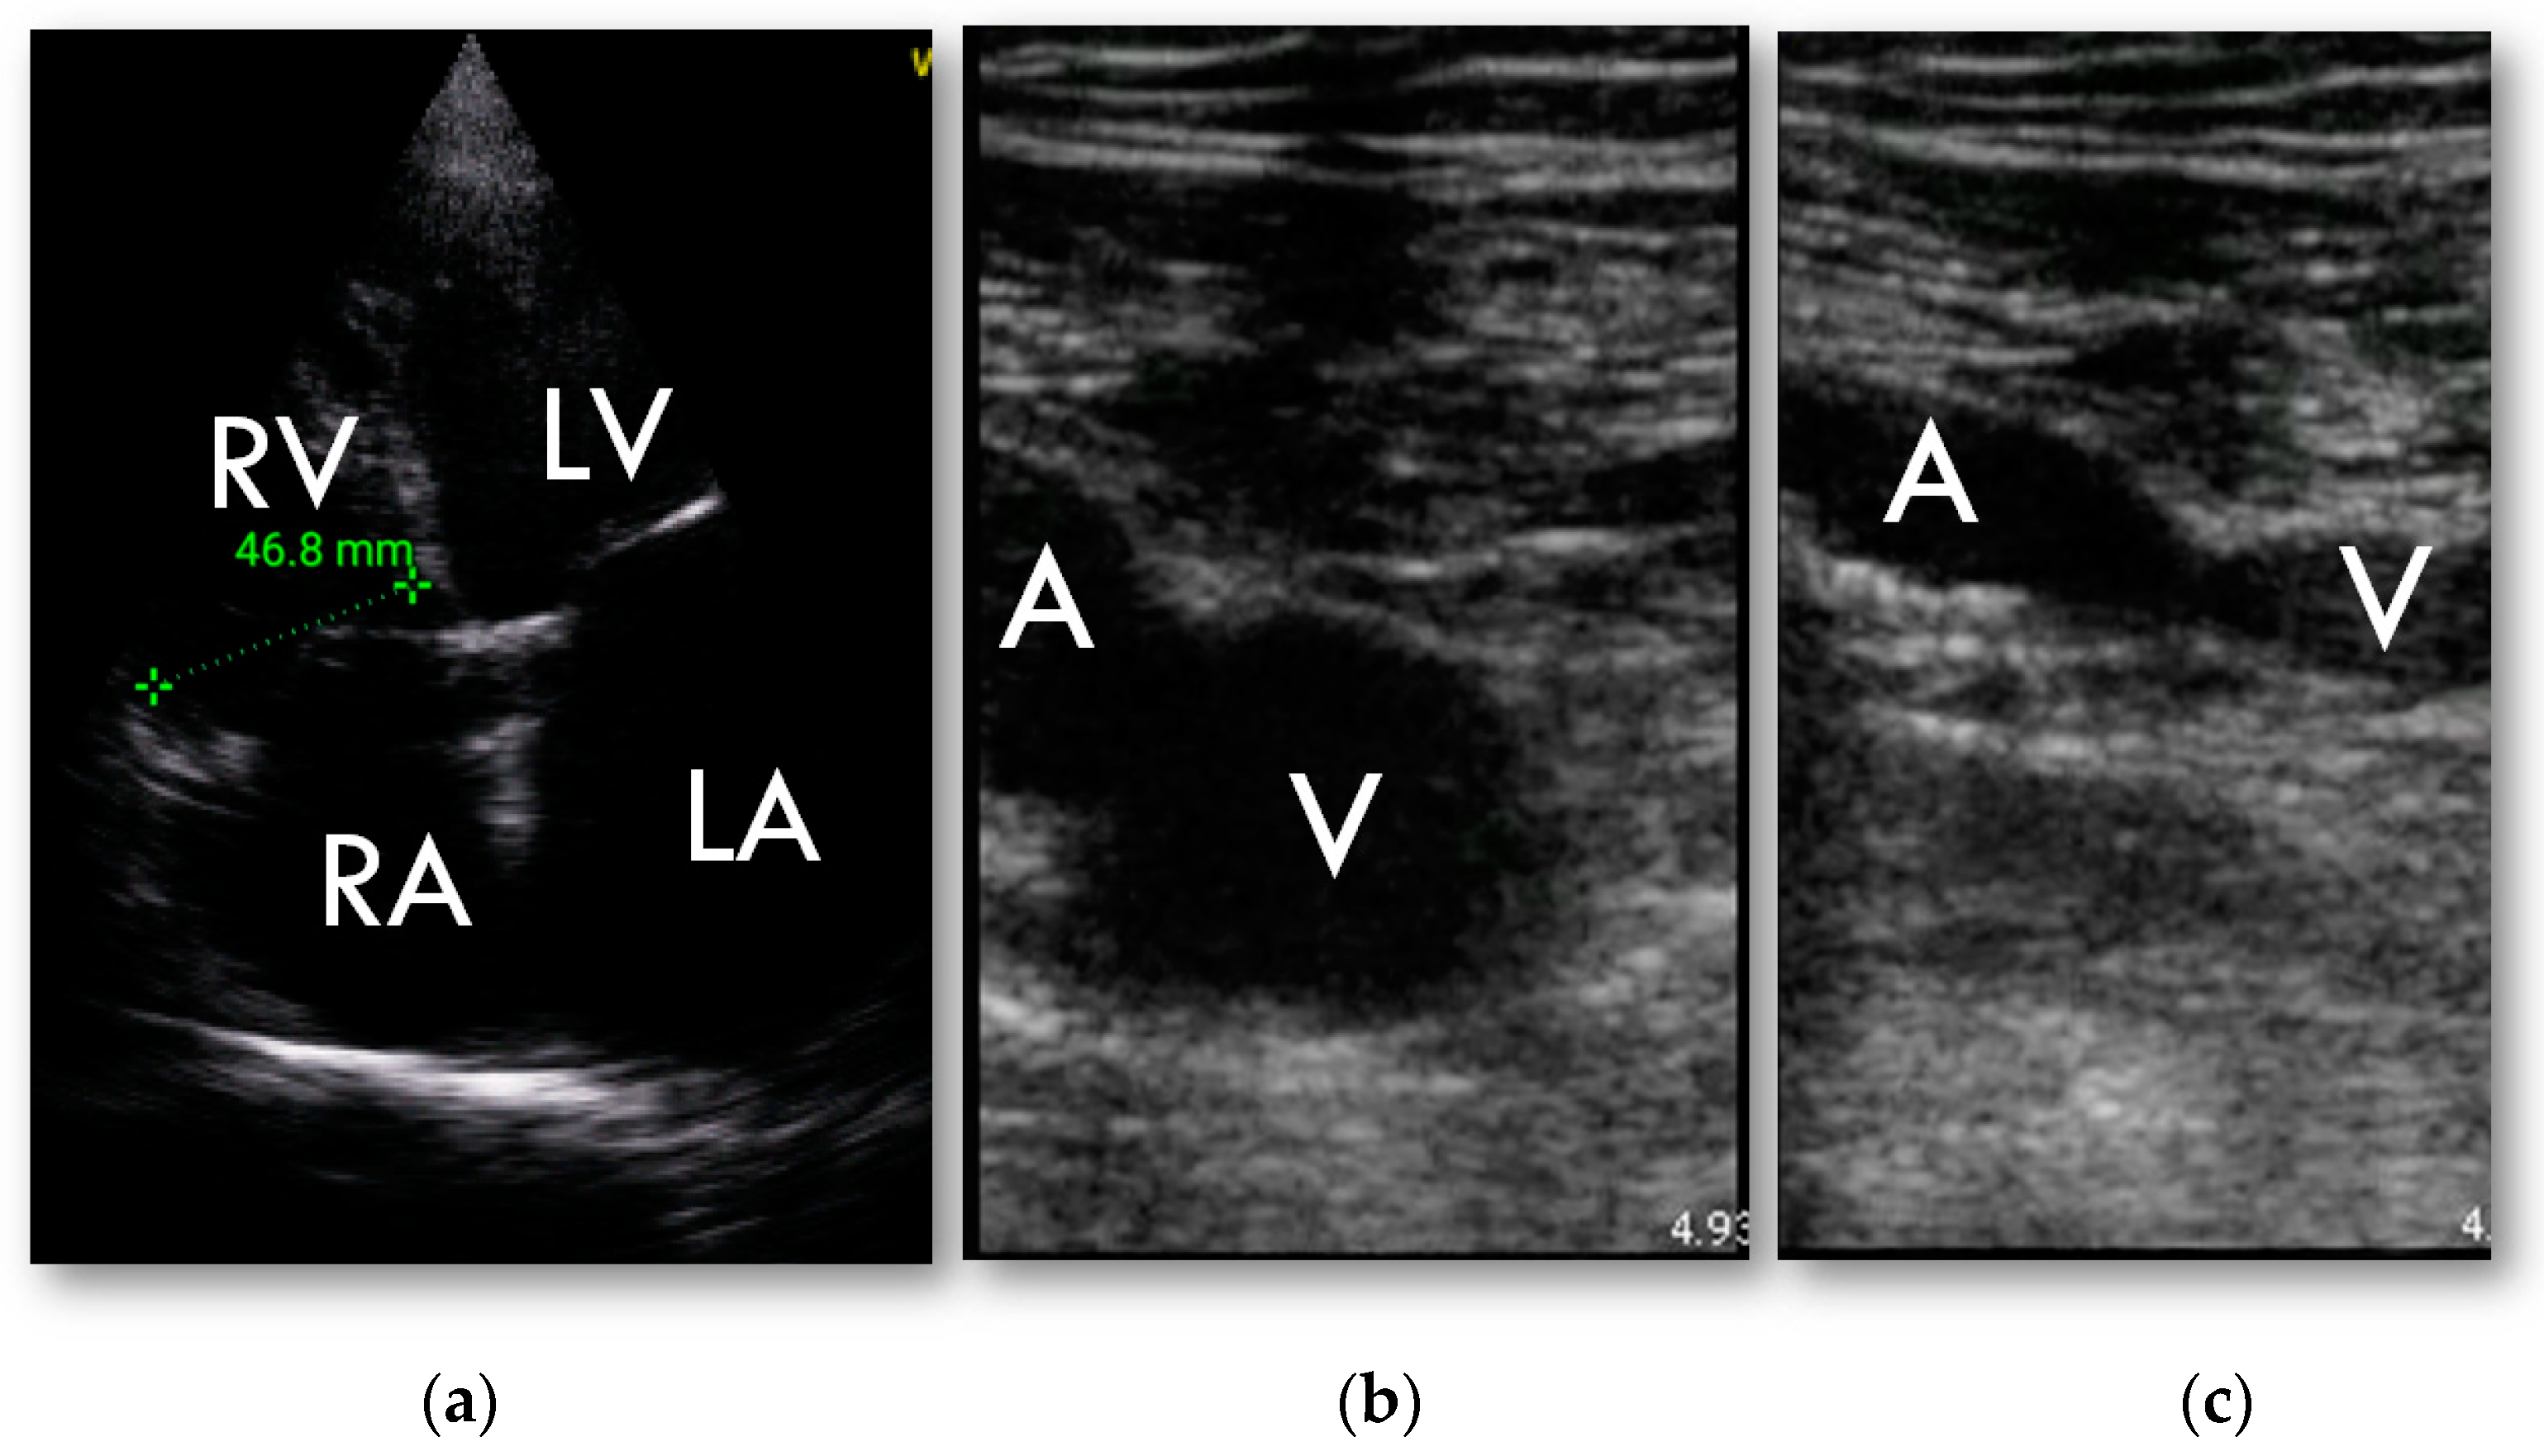

RV was found to be dilated in HUD examination in 27 patients (43%) and in 31 patients (49%) in full echocardiographic examination. Weighted kappa was 0.803 ± 0.074, 95% CI 0.665–0.953.

In both cases of positive CUS pulmonary embolism was confirmed in angioCT (Figure 4).

Figure 4.

HUD examination; (a)—RV focused 4-chamber apical view, basal dimension; (b,c)—compression ultrasound test of common femoral vein: (b)—without compression; (c)—abnormal examination in deep vein thrombosis. Vein is not entirely occluded.